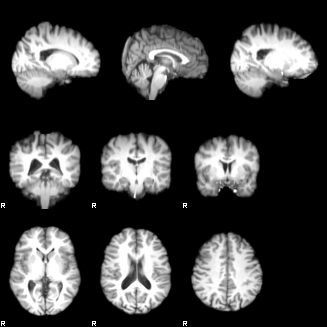

FAST

Set the Input image to be structural_brain (i.e. it is important to have run BET first). Turn on the Partial volume maps optional output images. Press Go. The outputs will be structural_brain_seg, structural_brain_pve_0, structural_brain_pve_1 and structural_brain_pve_2.